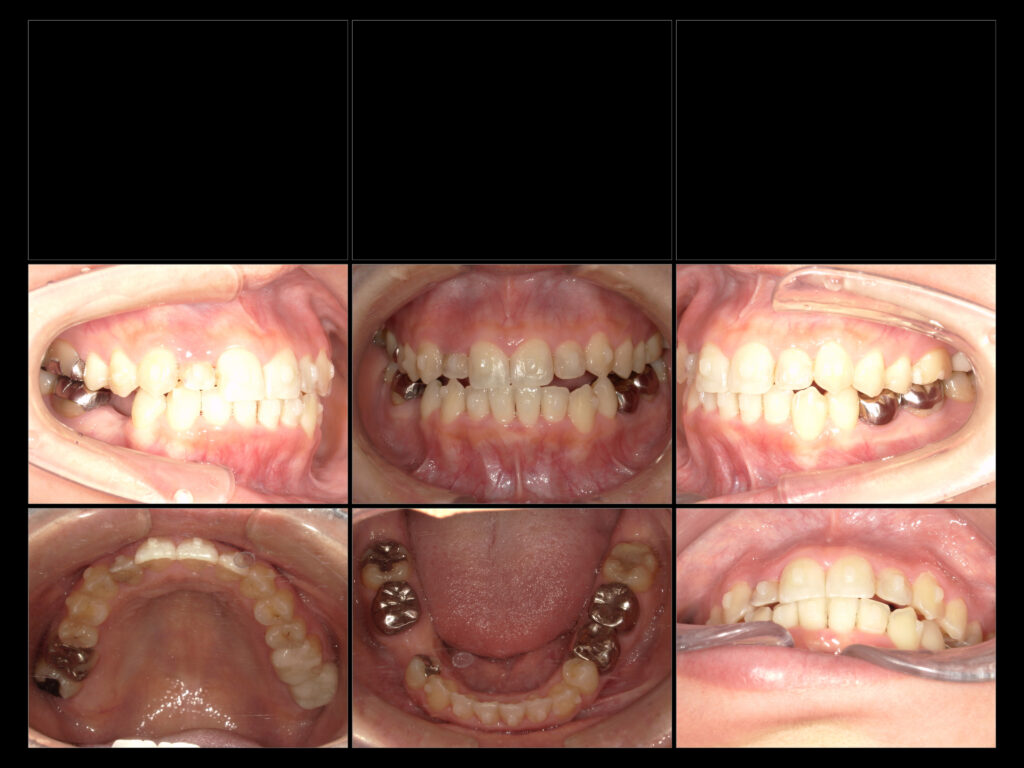

インビザGO症例

・主訴

上下の前後している歯が気になる

・治療内容

上下5~5インビザGO

・年齢

34歳

・性別

女性

・目的

叢生による歯の負担を減らす

・副作用

マウスピース交換時の歯の痛み

・治療期間

6ヶ月

・費用

40万~

・来院回数

7回(クリーニング除く)